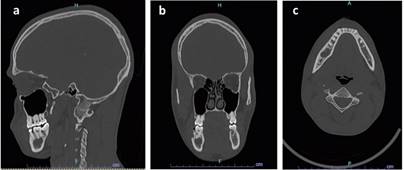

Imágenes por tomografía computarizada se observan 2 lesiones hipodensas aisladas una de la otra ubicadas en cuerpo (Fig. 2) y rama mandibular derecha (Fig. 3), una de ellas comprometiendo periapice de diente 18, ambas lesiones de 1.5 cm de diámetro aproximadamente.

Respecto a los estudios imagenológicos, se encuentran principalmente la tomografía computarizada (TC) y, en casos seleccionados, la resonancia magnética nuclear (RMN), quienes juegan un papel importante en el diagnóstico y manejo3. Es necesario considerar radiológicamente diagnósticos diferenciales con lesiones mandibulares radiolúcidas como el ameloblastoma, asimismo, diferenciarlos de los quistes foliculares, relacionados con la corona de piezas incluidas1.